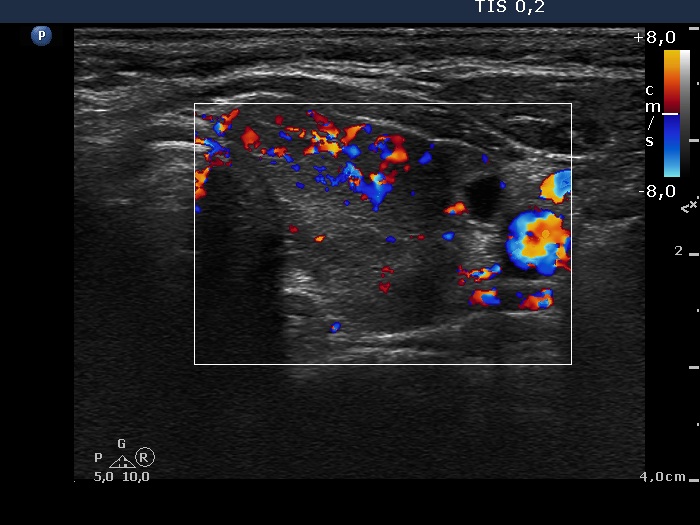

Follow-up investigation 18 months after the first visit (ultrasonographic picture 6)

Left lobe, longitudinal scan, color Doppler mode. The vascularization is moderately increased.